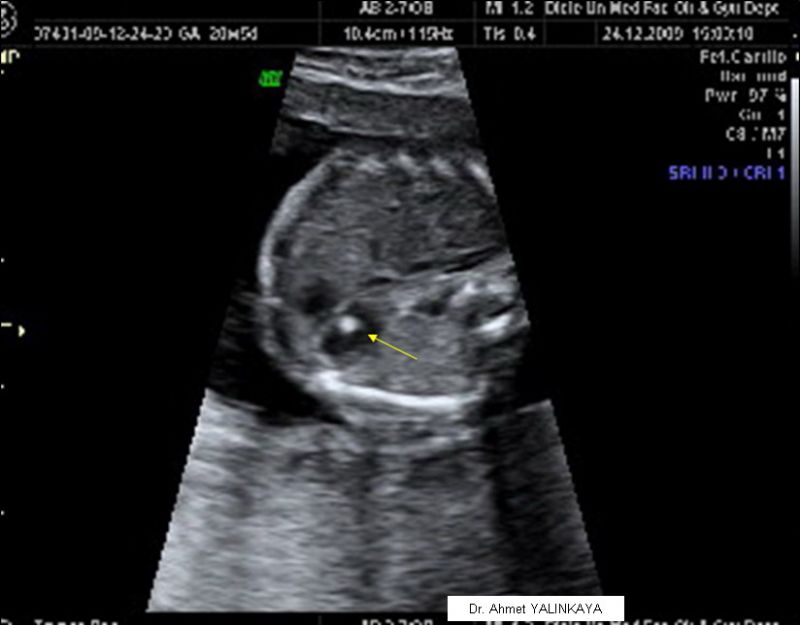

Bunlardan bir veya bir kaçında bölgesel doku yoğunluğu olduğunda ultrasonda daha parlak görülür. Bu incelemeler sırasında anne karnındaki bebeğin kalbinde beyaz ve parlak bir leke ile karşılaşılabilir. Bebeğin kalbindeki parlaklık var. Bugün kontrolde doktor bebeğin kalbinde bir parlaklık oldugunu soyleyıp haftaya cuma tekrar gel bakalım dedi.

Yapılan ultrasonlarda bebeğin kalp bölgesinde parlaklık kireçlenme ya da beyaz lekeler görülebilmektedir. Hamilelik süresi boyunca yapılan kontroller sayesinde anne adayının sağlık durumu ve bebeğin gelişimi net bir şekilde izlenebilmektedir. Anasayfa soru cevap gebelikte bebeğin kalbinde parlaklık olması tehlikeli mi. Bebeğin kalbindeki beyaz lekeye hamileliğin 4.

Hamilelik süresince yapılan kontroller ile annenin sağlık durumu ile bebeğin gelişimi izlenir. Aylarında daha çok rastlanmaktadır. Arkadaşlar ben 21 4 günlük hamileyim dün ayrıntılı ultrasona girdim ve doktor bebeğimin kalbinde parlaklık olduğunu söyledi başka bir anormallik olmadığını da soyledi kalpte parlaklık down sendromlu bebeklerde daha çok görülen bir şeymiş ve internetten araştırmaya başladım hemen. Anne karnında bebeğin kalbinin durmasının nedenleri anne karnında ölmesi nasıl anlaşılır ve anne karnındaki bebeğin kalp durma belirtileri hakkında bu yazımızdan bilgi alabilirsiniz.